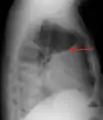

Pleural effusion Anteroposterior Chest X-ray of a pleural effusion. The A arrow shows fluid layering in the right pleural cavity. The B arrow shows the normal width of the lung in the cavity